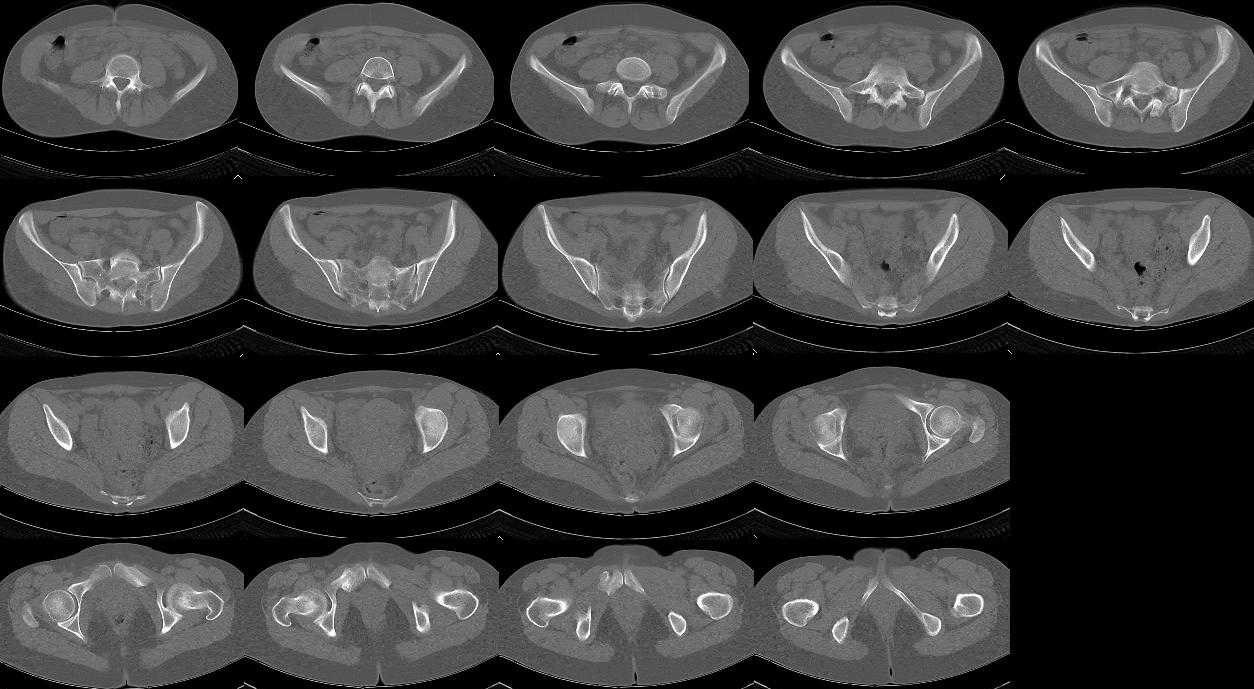

13/03/03 |  13/03/03 |  13/03/03 |  15/09/06 |  15/09/06 |  07/03/07 |  07/03/07 |  19/12/06 | К нам в клинику поступила пациентка 30 лет с диагнозом: Постравматическая ротационная стабильная деформация тазового кольца. Относительное укорочение левой н\конечности на 1 см. Левосторонний компенсаторный сколиоз 2 ст. Болевой синдром. травма автодорожная в январе 2003г. Пассажирка переднего сидения ваз 2109. лечились положением по Волковичу. С марта 2003 года жалуется на боли в тазу, ппояснице усиливающиеся при движении.В настоящее время жалобы на боли в области крестца, КПС больше слева, в пояснично-крестцовом отделе позвоночника. неприятные ощущения, щелчок при выпрямлении правого тазобедренного сустава из положения полного сгибания. боли в тазу появляются при ходьбе ч\з 100 м, так же при вставании из положения сидя, после сидения в течении 2-3 часов. при ходьбе более 100 м появпяется зябкость стоп больше справа. ходит при помощи трости в правой или в левой руке. без трости боли появляются сразу после начала ходьбы. пальпация болезненна в паравертебральных точках средне-грудного и пояснично-крестцового отделов позвоночника, КПС с обеих сторон. Объем движений в тазобедренных суставах полный.правый КПС заблокирован. симптомы натяжения с обеих сторон отрицательны.С 2003г. лечится консервативно, получала ЛФК, массаж, физиолечение - без эффекта. в 2005г. лечилась в санатории с ортопедическим уклоном, получала плавание в минеральной воде, магнитотерапия, массаж, ЛФК. отмечала умеренное улучшение в течении 2 недель.Вопросы:надо ли оперировать, т.е. устранять относительное укорочение левой н\конечности и как?Если не оперировать, то как лечить консервативно?Р-граммы, КТ прилогаются.

просьбе. досылаю КТ, фуккциональные Р-граммы пояснично-крестцового отдела позвоночника, фото пациентки.

Уважаемый Алексей. Описанные Вами клинические проявления указывают на нестабильность левого крестцово-подвздошного сочленения. Такие больные встречаются не редко (за последние 6мес.в нашей клинике оперировано 3 больных со сроками давности от 6мес. до 1 года). К сожалению рентгенологически их трудно обьективизировать. На КТ это проявляется артрозом и костными разрастаниями КПС. В Вашем случае рентгенограммы и представленные томограммы ничего не дали. Можно попробовать посмотреть связочный аппарат КПС на МРТ хотя не уверен что Вы получите окончательный ответ. Если Вы будете убеждены в этом диагнозе то выход один костно-пластический артродез левого крестцово-подвздошного сочленения с фиксацией канюлированными шурупами. Заманчиво конечно и устранить ротационное смещение половины таза, но это на Ваше усмотрение.

почему она должна возникнуть? Сломан вроде крестец, хотелось бы посмотреть функциональные снимки таза.

Уважаемый Максим. Снимки от 7.03.07 и есть функциональные, т.е. стоя на правой, и левой ноге.